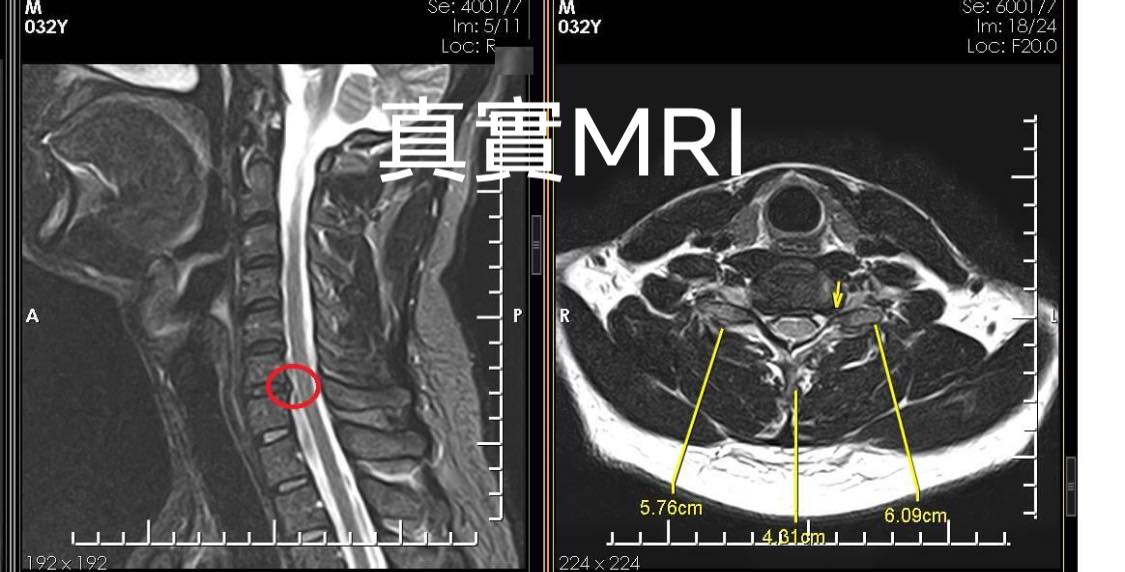

個案的蘇先生其實很年輕,三十出頭,會有這種嚴重的病狀要從6-7年前開始說起,當時私人公司上班因長期姿勢不良而受傷,曾經在復健科做過電療幾個月的治療,時好時壞,來診前已經出現夜間睡覺疼痛、整天不定時抽痛,久躺大約一小時就開始抽痛、開車或騎車痛,特別是他反映騎單車左手麻到無法撥桿,在今年六月MRI證實神經根卡壓,經過同事賴先生介紹來門診諮詢

1.C6/C7神經根型左側卡壓

2頸椎小面關節紊亂

3胸廓出口症候群